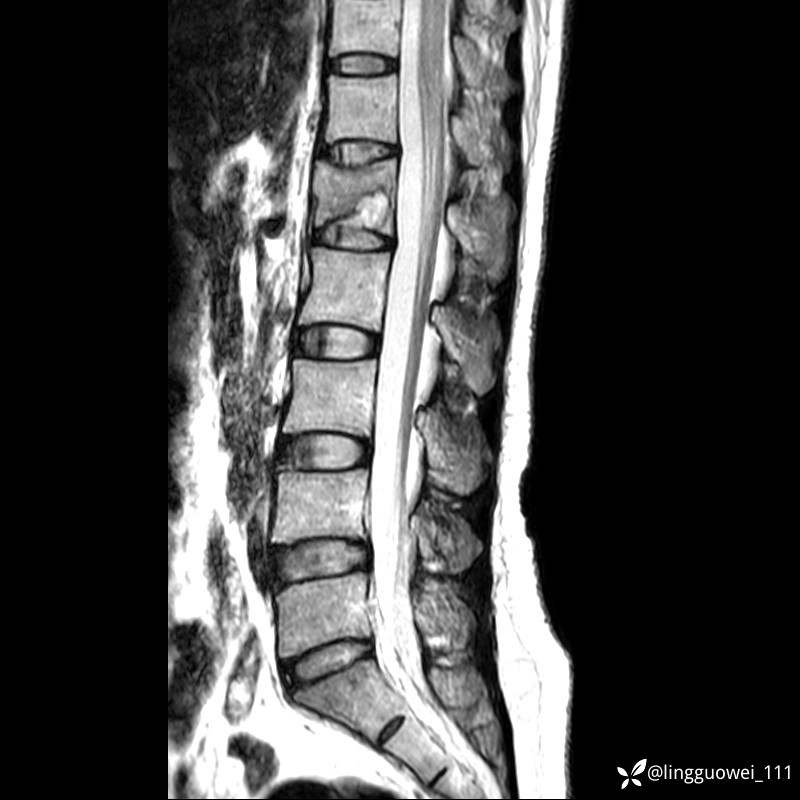

病例女,39岁,腰痛来诊,只有CT可能要鉴别诊断,而MR可以定性吗?

患者性别:女

患者年龄:39岁

主诉:腰痛

T1